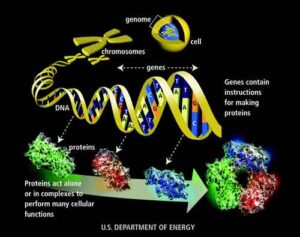

Uno studio finanziato da Telethon rimette in discussione le basi genetiche della distrofia facio-scapolo-omerale, malattia caratterizzata da debolezza muscolare progressiva...